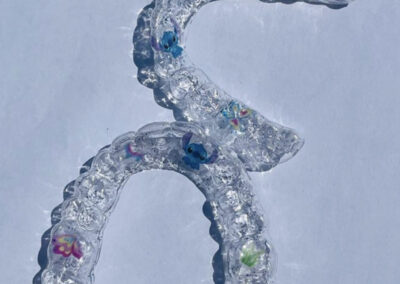

Contentions orthodontiques

Les contentions orthodontiques sont des dispositifs orthodontiques utilisés pour maintenir les dents dans leur position nouvellement corrigée après un traitement orthodontique. Ces dispositifs peuvent être fixes ou amovibles, et sont généralement recommandés pour être portés pendant une période de temps prolongée, voire indéfiniment.